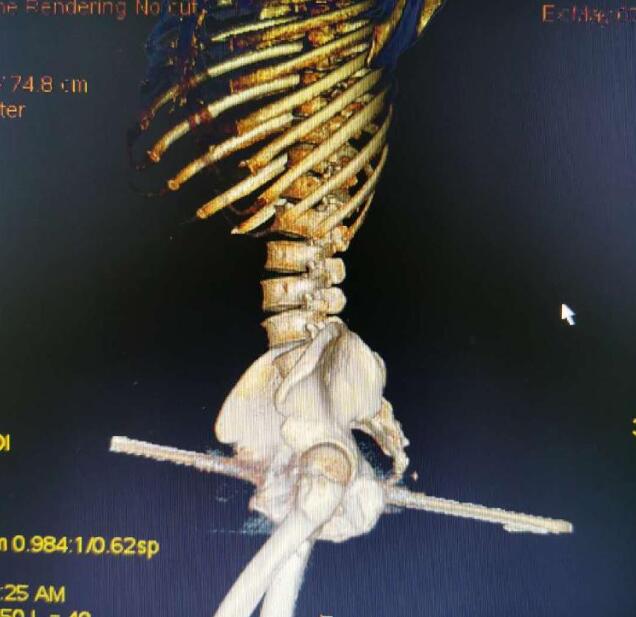

到達(dá)醫(yī)院后,消防員們被醫(yī)院工作人員帶到手術(shù)室外,按要求換好衣服后進(jìn)入手術(shù)室,“當(dāng)時看見一名男子側(cè)躺在手術(shù)臺上,一根鋼筋從臀部穿過男子身體。” 天文特勤站隊長助理耿家家說,據(jù)他目測,臀部那一側(cè)鋼筋裸露在外有20厘米長,另一側(cè)裸露在外10厘米左右,鋼筋直徑在1.5厘米左右。后經(jīng)測量,鋼筋長度在45厘米左右。

據(jù)了解,被鋼筋刺穿身體的男子44歲,當(dāng)天在工地作業(yè)時,不小心從1米多高的地方摔落,被地上豎立的鋼筋從右臀部向前側(cè)貫穿。

“雖然鋼筋刺穿了身體,但幸運(yùn)的是避開了血管、坐骨神經(jīng)、股動脈等重要位置!敝貞c市東南醫(yī)院骨科副主任譚云說,經(jīng)過前期治療患者的生命體征比較穩(wěn)定,院方經(jīng)過會診提出兩種方案,一是將右臀部表面組織全部切開,露出鋼筋。另一中方案就是將鋼筋從身體內(nèi)抽出。

“考慮到第一種方案對患者損傷較大,決定采取第二種方案。”譚云說,雖然鋼筋在工地已經(jīng)被截斷,但還是留下不少,并且鋼筋為螺紋鋼,如果按正常的方式抽出,會帶出部分體內(nèi)組織,對患者造成更大的傷害,為了最大限度減少患者損傷,也方便操作,決定求助消防用專業(yè)工具剪切。